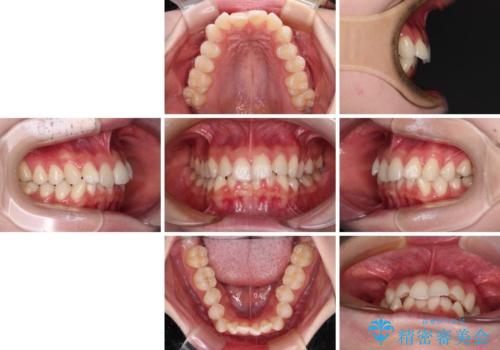

- 前歯のデコボコと下の前歯が隠れてしまう咬み合わせを気にして来院された患者様です。

インビザラインによる上下歯列の拡大と、IPR(歯と歯の間を削る)にるスペースの獲得により、口元のデコボコとディープバイトを改善することとしました。